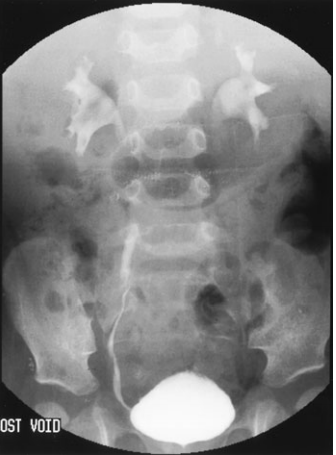

painful condition occurring when the foreskin gets retracted and trapped behind the glans and, because of edema and venous congestion, cannot be relocated into its normal position.,  ## Vesicoureteral Reflux After her first urinary tract infection, a 1-year-old has a voiding cystourethrogram with findings shown below. Which of the following is the most appropriate treatment option?

The radiograph shows reflux into the ureters and into the kidney, with dilation of the renal pelvis, making the diagnosis of vesicoureteral reflux. The higher the reflux into the renal system, especially if the renal pelvis is dilated, the more likely it is for renal damage to occur; the grading system is based upon these radiographic observations.

Grade I VUR is reflux of urine into an undilated ureter.

Reflux into the ureter and collecting system without dilatation is called grade II.

Grade III lesions have dilatation of the ureter and collecting system without blunting of the calyces.

Grade IV lesions are characterized by blunting of the calyces

Grade V lesions demonstrate even more dilatation and tortuosity of the ureter.

Low-grade lesions (grade I and grade II) are conservatively managed with close observation, daily low-dose antibiotics, and urinalyses and cultures every 3 to 4 months. Grade V lesions (and some grade IV lesions) require surgical reimplantation of a ureter if the findings persist. Lesions in between these two extremes are treatment dilemmas.